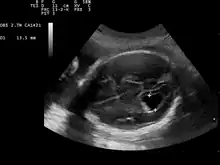

Prenatal ultrasound showing a well defined hypoechoic lesion corresponding to a choroid plexus cyst

Choroid plexus cysts (CPCs) are cysts that occur within choroid plexus of the brain. They are the most common type of intraventricular cyst,[1] occurring in 1% of all pregnancies.[2]